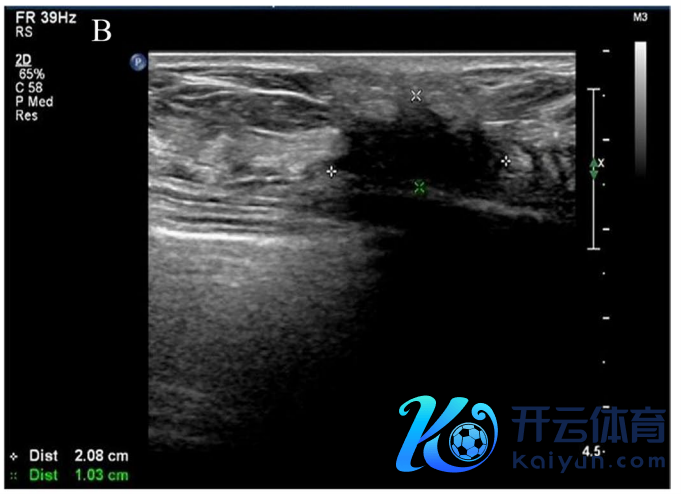

乳房和腋窝超声查抄:右乳7点乳头旁可见一大小约2.1 cm×1.0 cm的低回声团,样式不清且怪异正,内有点状强回声。可见右腋窝淋凑趣儿回声,约1.2 cm×0.7 cm,以皮质回声为主。

超声诊断:右乳肿块,BIRADS-US分级:4C级。右腋窝淋凑趣儿肿大(图1B,C)。

图1B,C. 乳腺超声示右乳7点乳头旁约2.1 cm×1.0 cm低回声团,神志怪异正,边界不清,内有点状强回声,CDFI:可见血流信号。